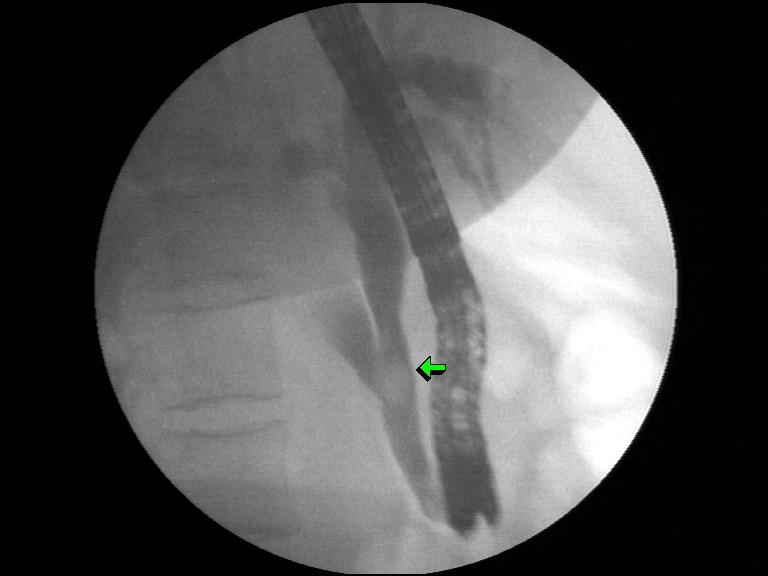

45 year female presented with complaints of pain in abomen with normal liver function test and ultrasound showing dilated bile duct with 10 mm stone in the lower part.Patient has no complaints of fever or back pain.

ERCP was done to remove the stone from the bile duct.Patient was sent bacl for laproscopic cholecystectomy and advised to come for removal for stent removal, a month later.